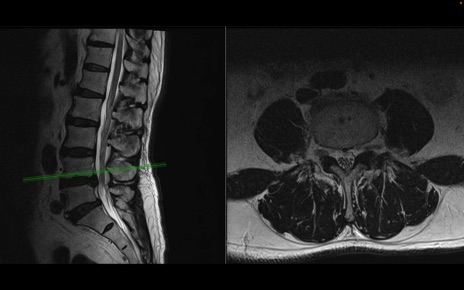

【症例】70歳代男性

【主訴】左下肢痛

【現病歴】2週間前くらいから腰痛、左下肢痛あり。左臀部から大腿、下腿外側のしびれが常時ある。歩行とともに同部位の痛みあり。

【身体所見】Lasegue70-/60+、Bragard-/±、PTR ±/±、ATR -/-、IP 5/5、TA 5/4、TS 5/5、EHL 右第1足趾なし/3、FHL 5/5、hypersthesia(-)、足背動脈触知良好

異常所見と診断は?